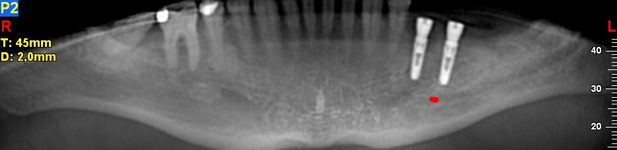

NewTom Implant Planing

NewTom Implant Planing

Jedná se o plánovací program, který využívá dat získaných při vyšetření pomocí přístroje New Tom. Tento program umožňuje tříprostorovou počítačovou simulaci při plánování pozic implantátů.

Součástí programu je i databáze, ve které mohou být uloženy všechny typy implantátů od všech výrobců, včetně jejich délek, průměrů i tvarů.

Lékař si vytvoří všechny typy zobrazení potřebných pro naplánování – tedy 2D snímky (panoramatický), příčné řezy i 3D model.

Vidí zde i důležité anatomické útvary – čelistní dutinu, průběh nervu atd. Po proměření množství kosti – šířky i výšky vybere z databáze vhodný typ implantátu a umístí ho do požadované lokality.

Ihned vidí jeho pozici ve všech 3 rovinách a na všech snímcích i 3D modelu. Může upravovat podle potřeby jeho pozici, sklon atd.

Všechny vybrané a správně umístěné simulované implantáty se ukládají do „počítačové karty“ pacienta s jejich pozicí, délkou, průměrem, typem i sklonem.

Lékař i pacient tedy ještě před vlastní operací vidí, jak by mělo ošetření probíhat a vypadat.